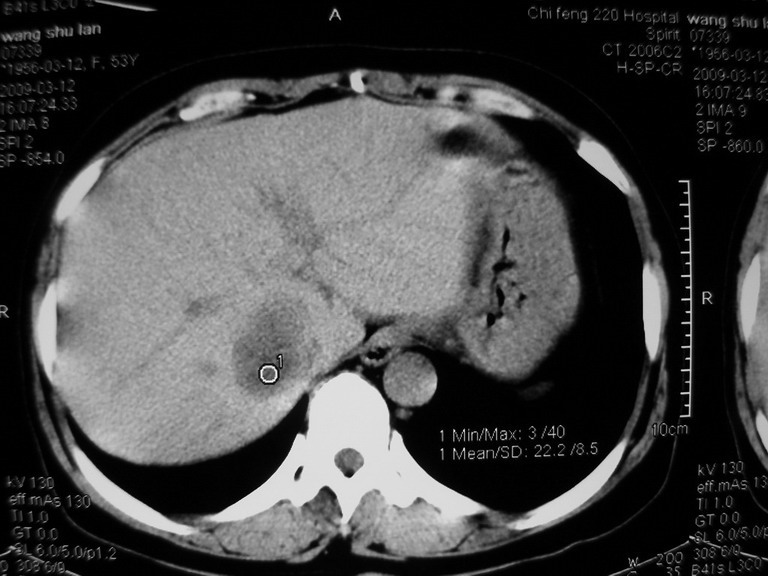

患者,女性50岁,上腹部不适2年余,既往多次腹部彩超未见异常,今日上午在我院查彩超发现肝右叶囊实性病变,外院辅助检查,afp,cea,ca199, 都在正常范围内,无肝炎史否认肿瘤史,生活在牧区

考虑肝癌。缺少延迟片。

接着往下一贴看,有静脉期和延迟期,在看看和下腔静脉及十二指肠的关系,腔静脉内是不是栓子?

考虑肝右叶与尾叶交界区肝癌(部分外生),侵犯下腔静脉并下腔静脉瘤栓形成。

肝包虫病可能性大